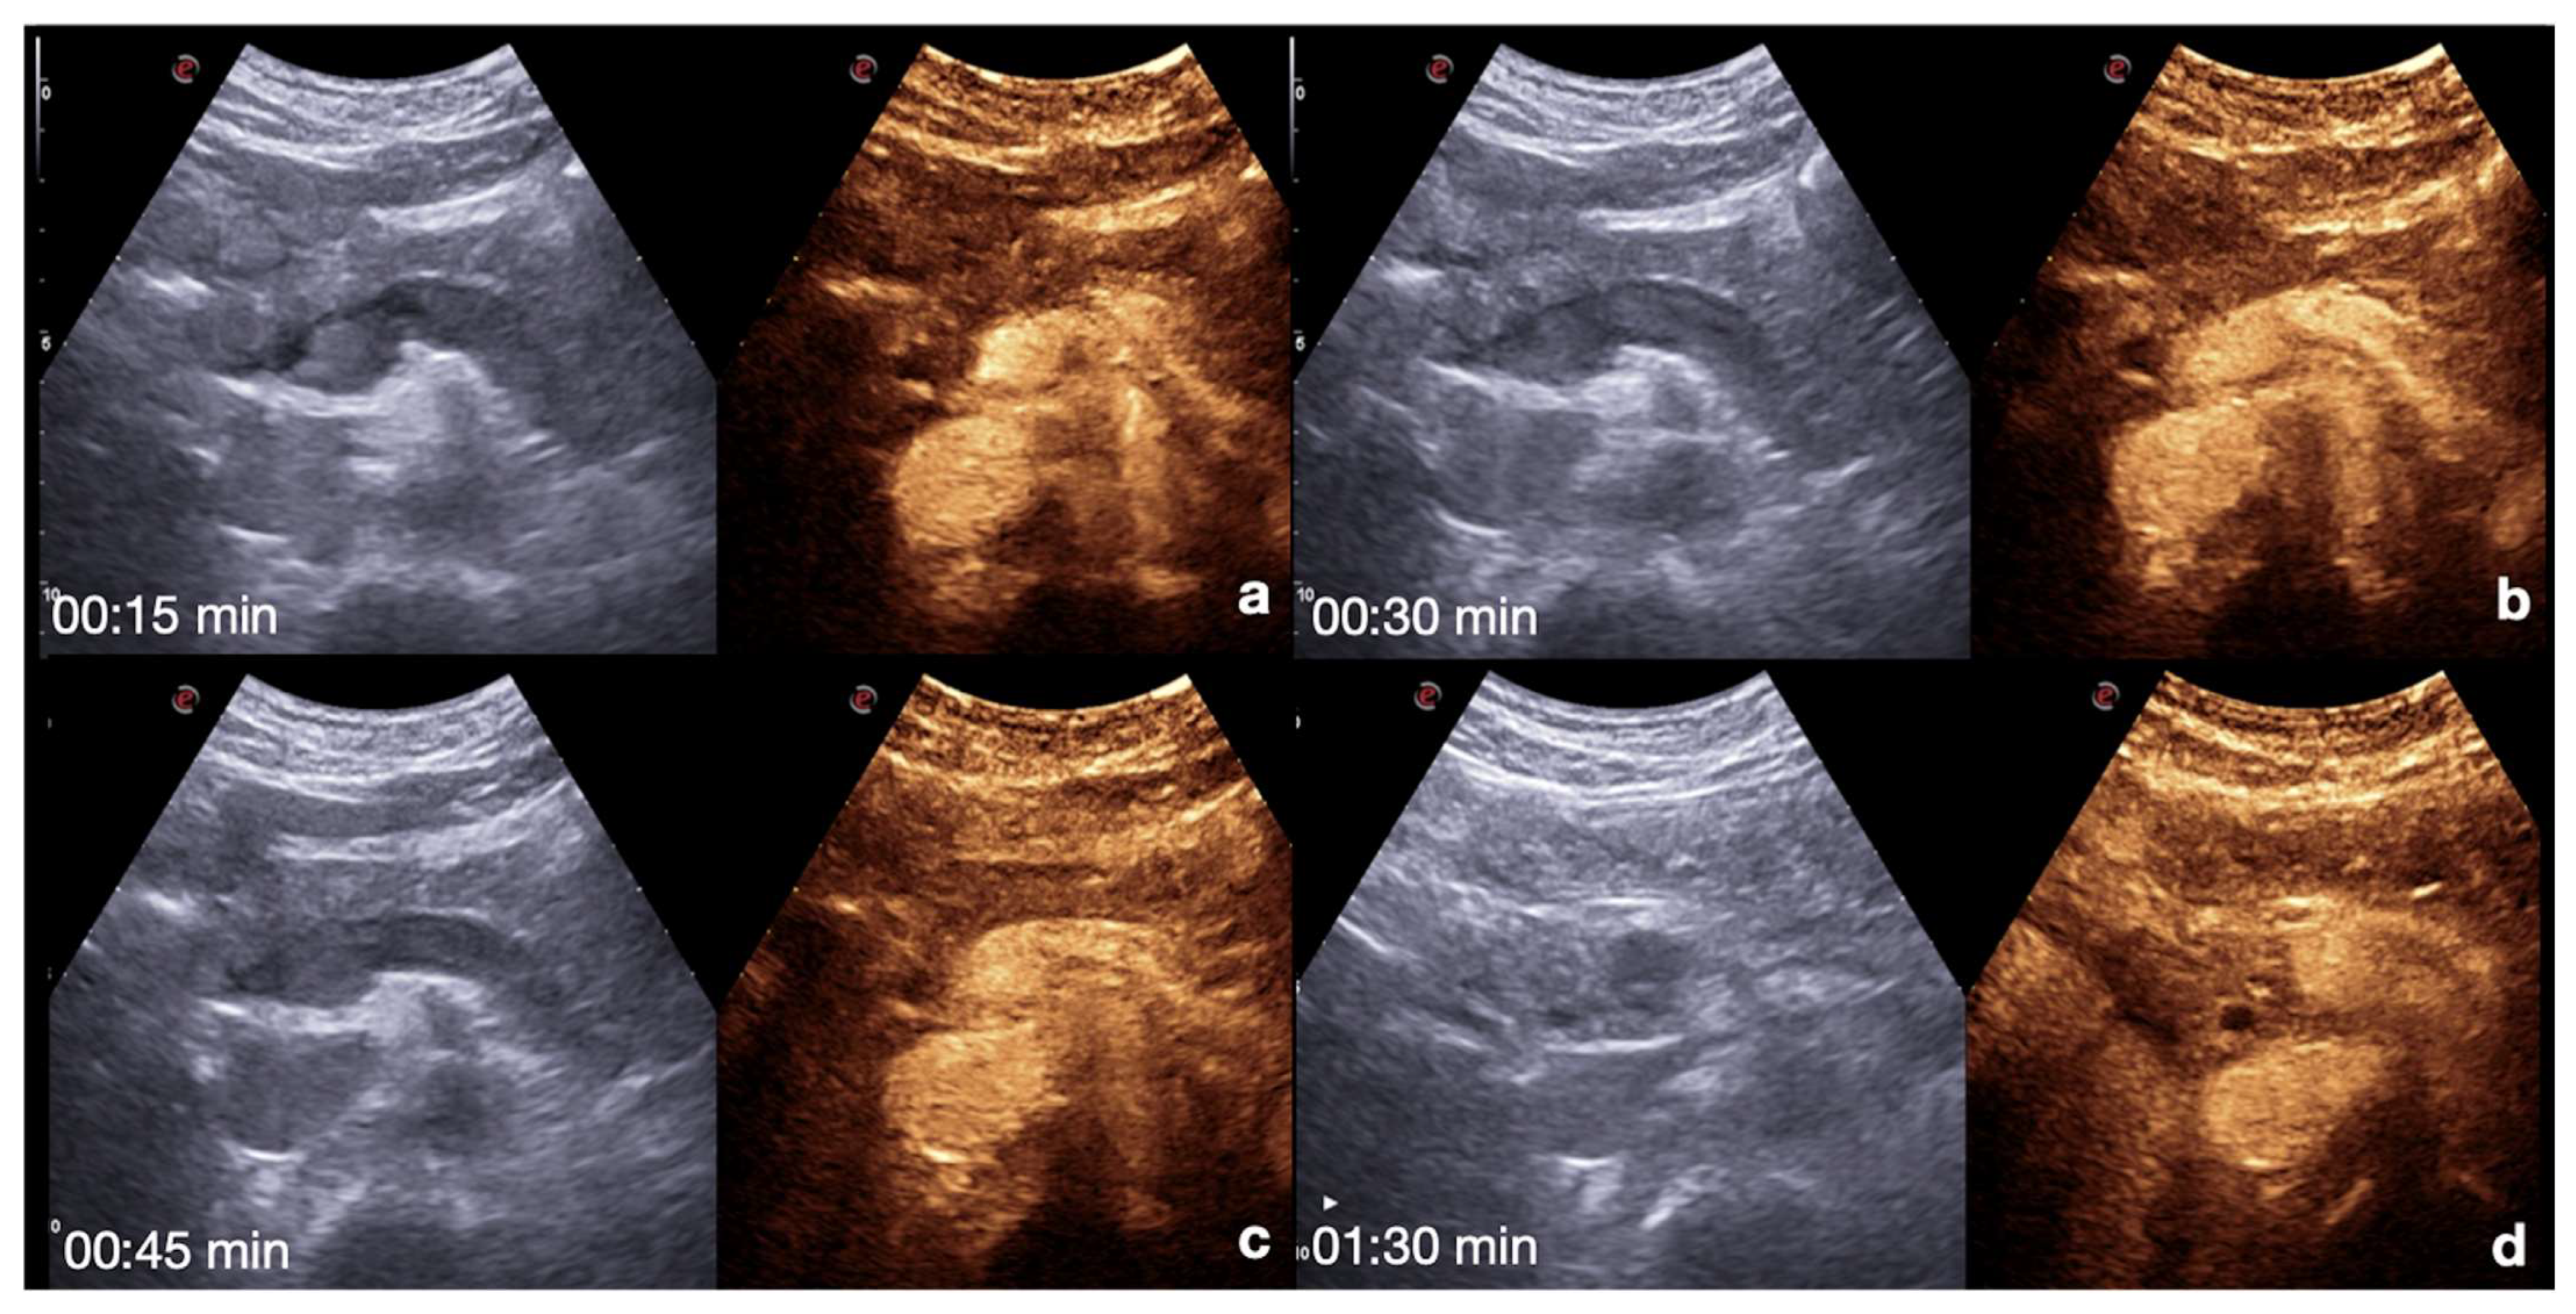

| Spleen | Arterial phase: 12–20 s. Venous phase: 40–60 s up to 5–7 min. The best moment to detect organ injury: venous phase. |